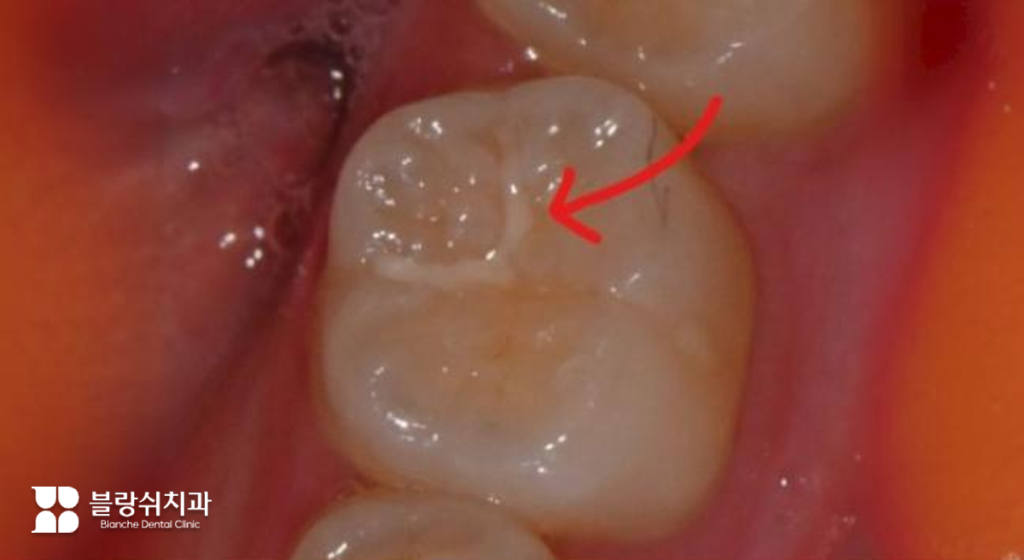

- 중기 단계: 상아질까지 침범 찬물이나 단 음식을 먹을 때 시린 증상이 나타납니다. 치료 시기를 놓치면 신경까지 빠르게 진행될 수 있어 인레이나 온레이 치료가 필요합니다.